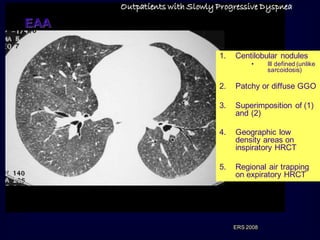

Outpatients with SlowlyProgressive Dyspnea EAA 1. Centilobular nodules • Ill defined (unlike sarcoidosis) 2. Patchy or diffuse GGO 3. Superimposition of (1) and (2) 4. Geographic low density areas on inspiratory HRCT 5. Regional air trapping on expiratory HRCT ERS 2008

• 65.